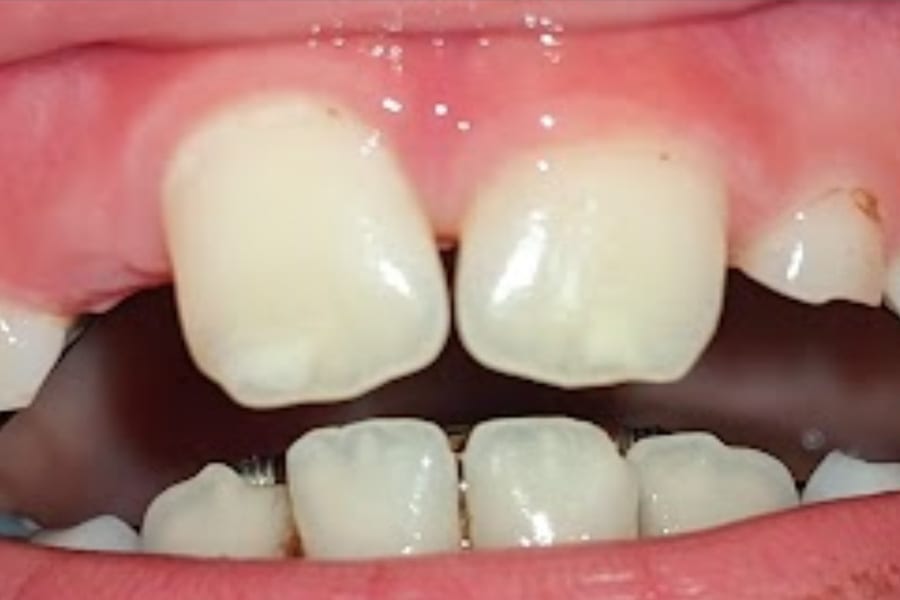

Lucas, an 8-year-old boy (now 10), presented with a history of significant developmental challenges, including ARM/VATER syndrome, multiple early surgeries, and enamel weakness with erosion. Orthodontic appliances, including an expander and, later, a Nance, complicated hygiene. Visual examination revealed white spot lesions on teeth Nos. 8 and 9.

Traditional management might include topical calcium-phosphate-based toothpastes, fluoride varnish, or resin infiltration. However, due to concern for the patient’s age and social development, treatment with Curodont was preferred. Curodont was applied following etching and drying, with Curodont Protect placed for 6 months. Adjuncts included use of a calcium-phosphate-based toothpaste, fluoride rinse, and power brushing.

At 6- and 12-month follow-ups, the lesions demonstrated visible shrinkage, hardened surfaces, and clinical arrest. Lucas tolerated the treatment well, with no anesthesia required. This case illustrates the use of guided hydroxyapatite generation in pediatric patients, providing both clinical efficacy and parental reassurance while preserving esthetic options for the future. (Figure 1 and Figure 2)